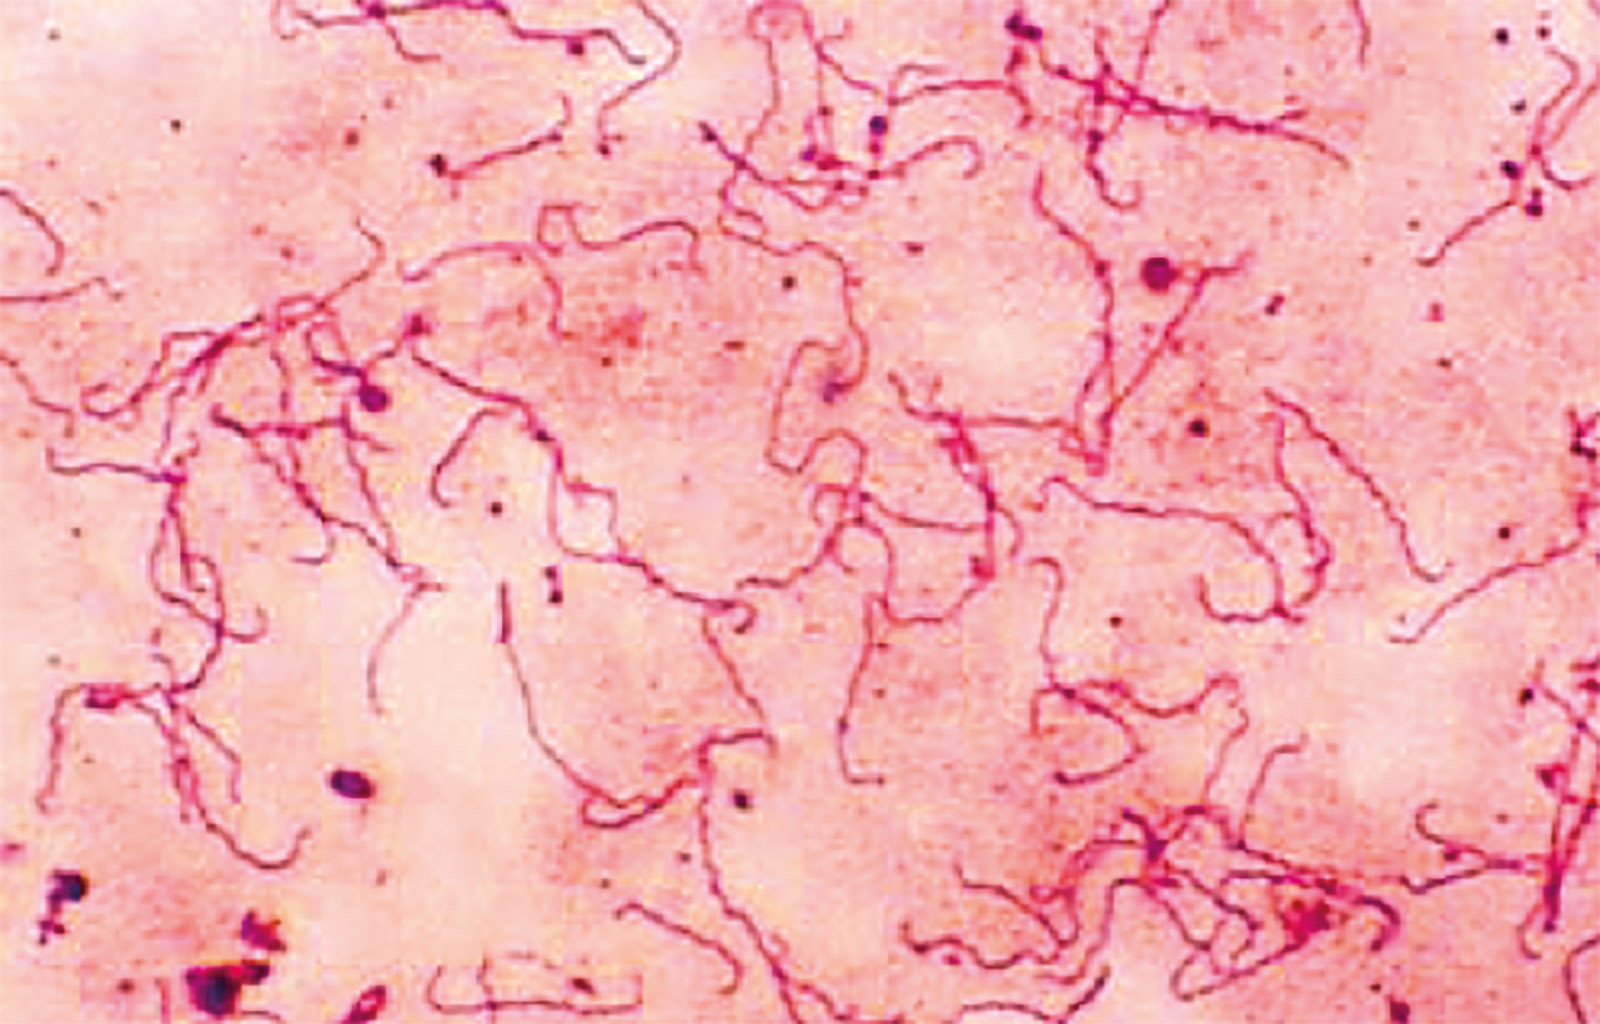

Лептоспиры: фотографии удивительных микроорганизмов

:max_bytes(150000):strip_icc():format(webp)/spirillum-56a09b3b3df78cafdaa32ecc.jpg)